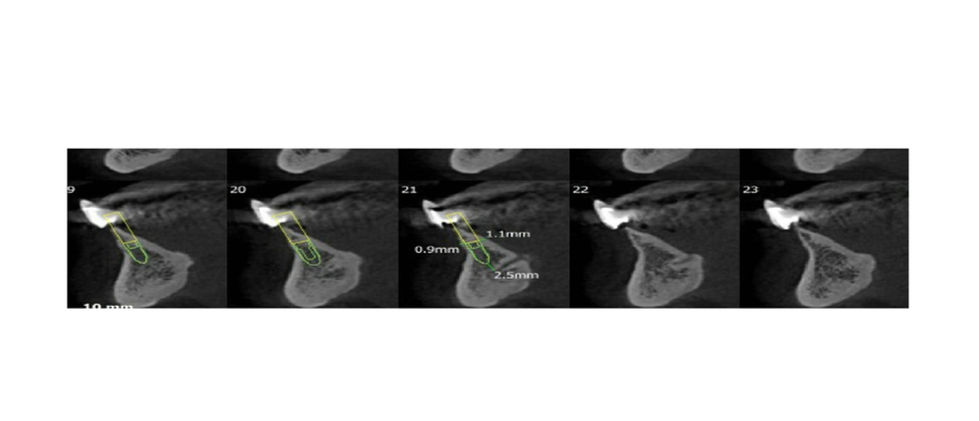

Sample cases